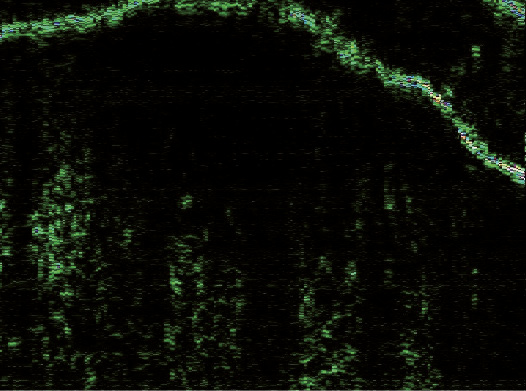

Эпидермис в очагах ББ определялся в виде полосы высокой эхогенности белого цвета с многочисленными желтыми и синими вкраплениями и в виде полосы зеленого оттенка, расположенной под ней. Его внутренний контур был четким и хорошо отграниченным от подлежащей дермы. В зависимости от ультрасонографической картины эпидермиса сканограммы очагов ББ были разделены на две разновидности. В 6 (75%) случаях (1-я разновидность) очаги представляли собой гиперэхогенную полосу неравномерной толщины, волнообразной формы с почкообразными отростками вглубь дермы (рис. 2). В 2 (25%) случаях (2-я разновидность) регистрировали гиперэхогенный слой одинаковой ширины на всем протяжении, с ровным внешним и внутренним контуром (рис. 3).

Рис. 3. Сканограмма болезни Боуэна (датчик 75 МГц). Гиперэхогенный эпидермис одинаковой ширины на всем протяжении, с ровным внешним и внутренним контуром (разновидность 2). Гипоэхогенная зона определяется в виде образования округлой формы с нечеткими границами